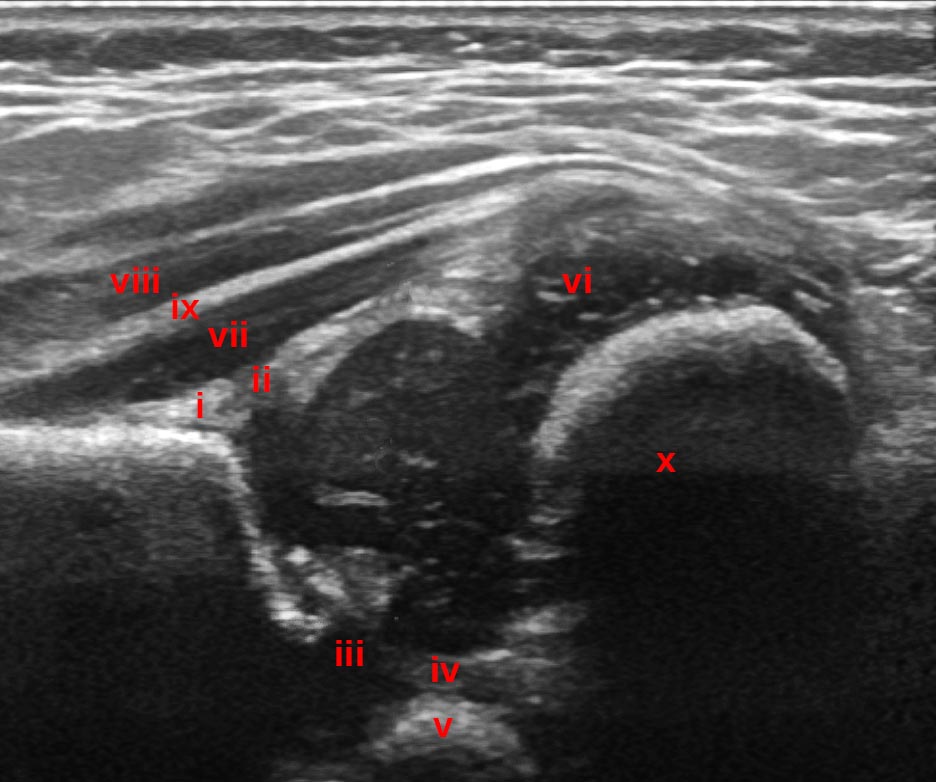

Further assessment for the following structures should be performed to ensure the correct plane has been obtained and that the image can be used:

1. The lower limb of the ilium

2. the horizontal (or vertical aspect of the Ilium) - straight and perpendicular to the ultrasound beam

3. The labrum

Further anatomical structures are:

1. Proximal perichondrium (Tendon of reflected head of rectus femoris, perichondrium of hyaline cartilage, and joint capsule fat deposit)

2. Perichondrial gap (distal capsule and perichondrium), ischio-femoral ligament

3. Triradiate cartilage

4. Ligamentum teres

5. Ischium

6. Greater trochanter

7. Gluteus minimus

8. Gluteus maximus

9. Intermusular septum

10. Femoral metaphysis